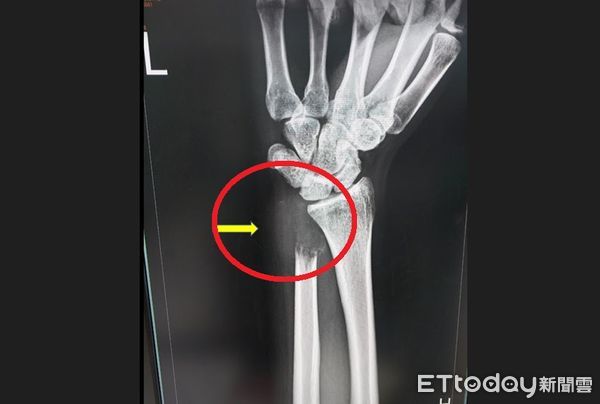

▲24歲男患罕見「骨巨細胞瘤第三期」,手無力就醫照X光:骨頭被癌細胞吃空。(圖/烏日林新醫院提供)

台中一名24歲業務陳先生,一年多前發覺運動打籃球時左手腕稍微不適,工作時搬重物漸漸無法出力,直至3個月前症狀逐漸明顯,摸到左腕外側腫起來且重壓時會有痛感,甚至舉不太起來,連拿杯子喝水也覺得吃力,就醫檢查竟發現是罕見的尺骨遠端「骨巨細胞瘤」第三期,X光片檢查左腕尺骨遠端被腫瘤吃空了一大塊,且發生病理性骨折,醫師將尺骨末端截骨,切除腫瘤後做韌帶重建手術,目前已順利出院。